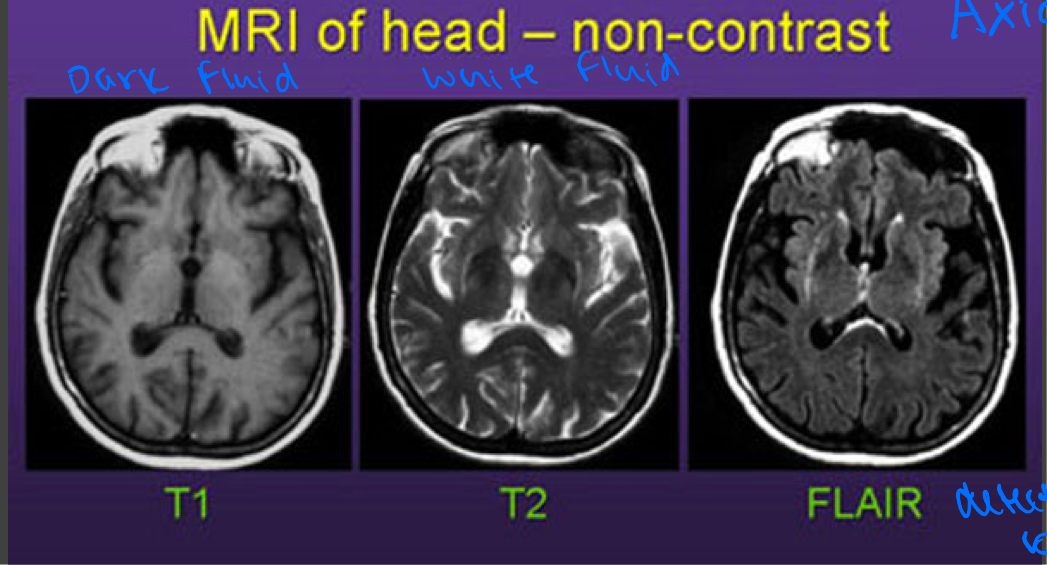

MRI: T1 weighted images

Highlights fat as bright

Muscles as intermediate

Water (blood, CSF) as dark

Brain- gray matter is darker than white matter

MRI: T2 weighted images

Highlights water as bright

Fat as slightly less bright

Muscle as intermediate

Brain- white matter is darker than gray matter

Comparison of the typical tissue appearances on T1 and T2

Comparison of MRI’s